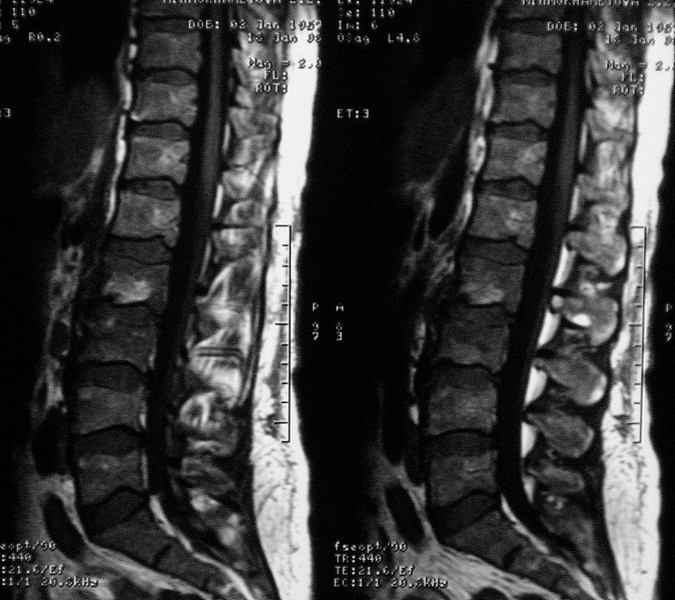

Отправляю MRI в динамике, снятые с пленки на фотоаппарат.